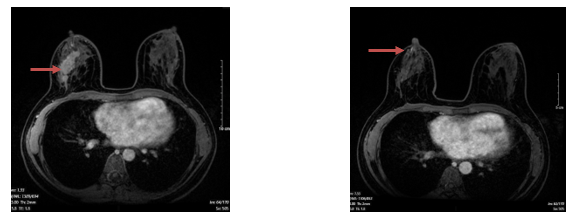

· Hạch hố nách bên phải,chặng I có vài hạch, có vỏ dày, kích thước lớn nhất 7x13mm

Hình 2. Hình ảnh chụp cộng hưởng từ tuyến vú. Hạch hố nách bên phải, có vỏ dày, kích thước 7x13mm (mũi tên màu đỏ)